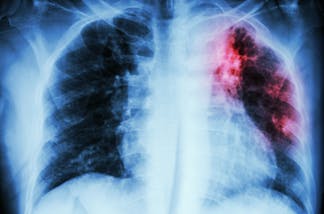

A microscopic view of Mycobacterium tuberculosis, the bacteria that causes tuberculosis. koto_feja/E+ via Getty ImagesAn outbreak of tuberculosis, or TB (tubercle bacillus) – a lung disease that is often accompanied by a hacking cough – began in January 2024 in Kansas City, Kansas, and two nearby counties and continues as of early March 2025. To date, 147 people have been reportedly diagnosed with TB in the outbreak, with 67 becoming ill. The remaining 80 people diagnosed with TB in Kansas contracted the illness but showed no symptoms, which is called a latent infection.

Mycobacterium tuberculosis is the organism that causes the disease tuberculosis in humans. The disease has been infecting humans for thousands of years. Researchers found evidence of the disease 9,000 years ago in the excavated remains of people who lived in the Eastern Mediterranean region during that time.